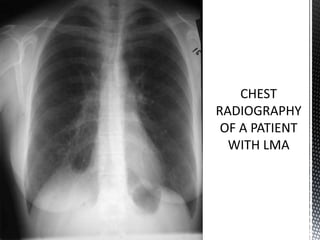

*Chest radiographs in lymphangioleiomyomatosis (LAM)

may be normal. Fine reticular or reticulo-nodular interstitial

infiltrate with preserved lung volumes is the most commonly

observed abnormality. Pleural effusions may be present.

Patients may present with pneumothorax.